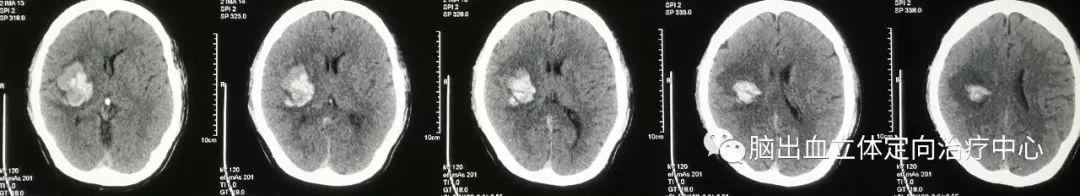

发病时CT:

第四天CT:

可见血肿呈分层现象,血肿周围水肿带明显,利用3D测量其各相关CT阈值。